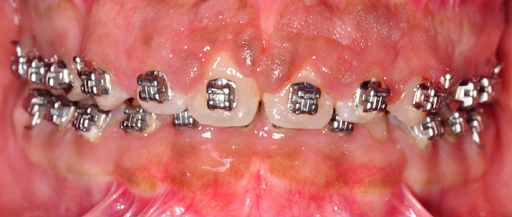

Close-up of a person's mouth with metal braces on teeth and overgrowth of gum tissue.

Before